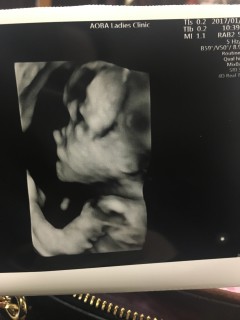

男の子です!! 初めて性別と顔がわかりました(*^^) 写真は顔の横に手をおいてるねんねポーズみたいに見えて可愛いー!!次の検診も楽しみ(*´ω`*)

最初この写真を見たときは顔の中心部分に見えるものを目・鼻だと勘違いしましたが、良く見ると左顔らしく、目・鼻は顔の左下にありました(*^_^*)

目を閉じてうつむいています。口は左腕で隠れています。